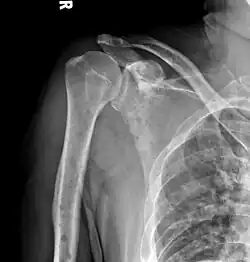

Humerus with multiple myeloma lesions -

Same humerus before, with just subtle lesions

The diagnostic examination of a person with suspected multiple myeloma typically includes a skeletal survey. This is a series of X-rays of the skull, axial skeleton, and proximal long bones. Myeloma activity sometimes appears as "lytic lesions" (with local disappearance of normal bone due to resorption) or as "punched-out lesions" on the skull X-ray ("raindrop skull"). Lesions may also be sclerotic, which is seen as radiodense.[76] Overall, the radiodensity of myeloma is between −30 and 120 Hounsfield units (HU).[77] Magnetic resonance imaging is more sensitive than simple X-rays in the detection of lytic lesions. An MRI may supersede a skeletal survey, especially when vertebral disease is suspected. Occasionally, a CT scan is performed to measure the size of soft-tissue plasmacytomas. Nuclear Medicine Bone scans are typically not of any additional value in the workup of people with myeloma (no new bone formation; lytic lesions not well visualized on nuclear bone scan).